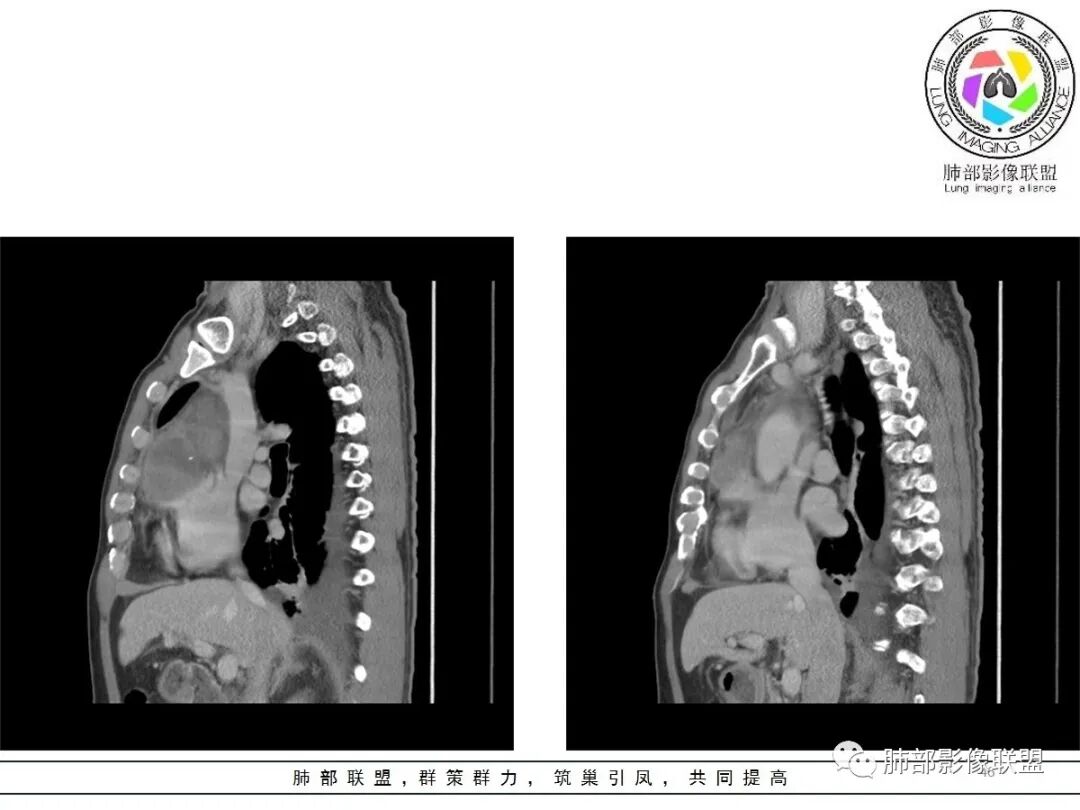

周围脂肪间隙密度增高,内部小点状很低密度影

右侧少量胸水

19日,4天后, 内部低密度影有,周围渗出增多,胸水增多

薄膜状强化

影像上周围病灶变化明显

常规肿瘤侵犯不支持,太快

应该是炎性病变渗出

脂肪密度明显,还有钙化、囊性病变,支持含脂质类病变破裂

周围是化学性炎症或出血所致

后期强化,可能与炎症有关

可能:1、肿瘤或瘤样病变破裂出血或内部物质外溢所致2、炎性病变所致

肿瘤样病变破裂所致纵隔炎应该没错

南边:肿瘤或肿瘤样病变破裂所致纵隔炎,这是大方向

2.胸膜掀起,右侧内乳动脉略增粗,定位右前上纵隔内占位。

3.右上纵隔囊实性占位,边界清楚。中央见点状脂肪密度影,边缘见一点状钙化影,增强不均匀环形强化。

4.四天内病灶变化快,块影增大且不规则,包膜似不完整,边界不清,上份可见浸润或渗出,与周围心脏大血管及心包等间隙不清。胸水增多。